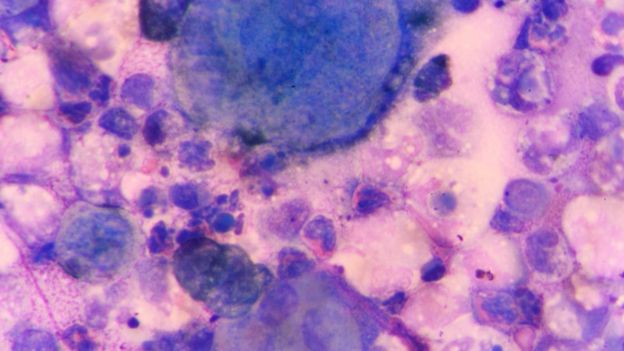

Las cosas buenas que hacen los virus superan por lejos a las malas, dice el epidemiólogo Tony Goldberg. GETTY IMAGES